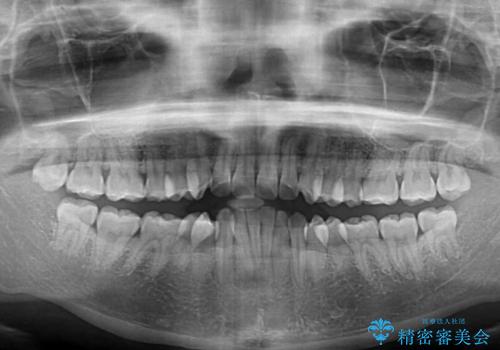

上下顎ともに前突した歯列であったので、上下ともに左右の第1小臼歯4本を抜歯し、ワイヤー装置にて矯正治療を行うこととしました。